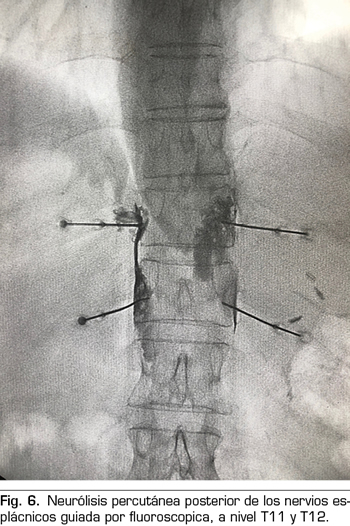

Se realiza mediante un abordaje posterior retrocrural, normalmente guiado por fluoroscopia (Figura 6). Las lesiones pueden llevarse a cabo mediante radiofrecuencia convencional o utilizando agentes neurolíticos como en el plexo celiaco.

– Abordaje retrocrural: abordaje que clásicamente se ha descrito tanto para el bloqueo del plexo celiaco (a nivel L1) como para los nervios esplácnicos. En el abordaje retrocrural puro, el paciente se coloca en decúbito prono y se localizan los cuerpos vertebrales de T11 y T12, avanzando las agujas hasta el tercio anterior de estos y bloqueando así los nervios esplácnicos.